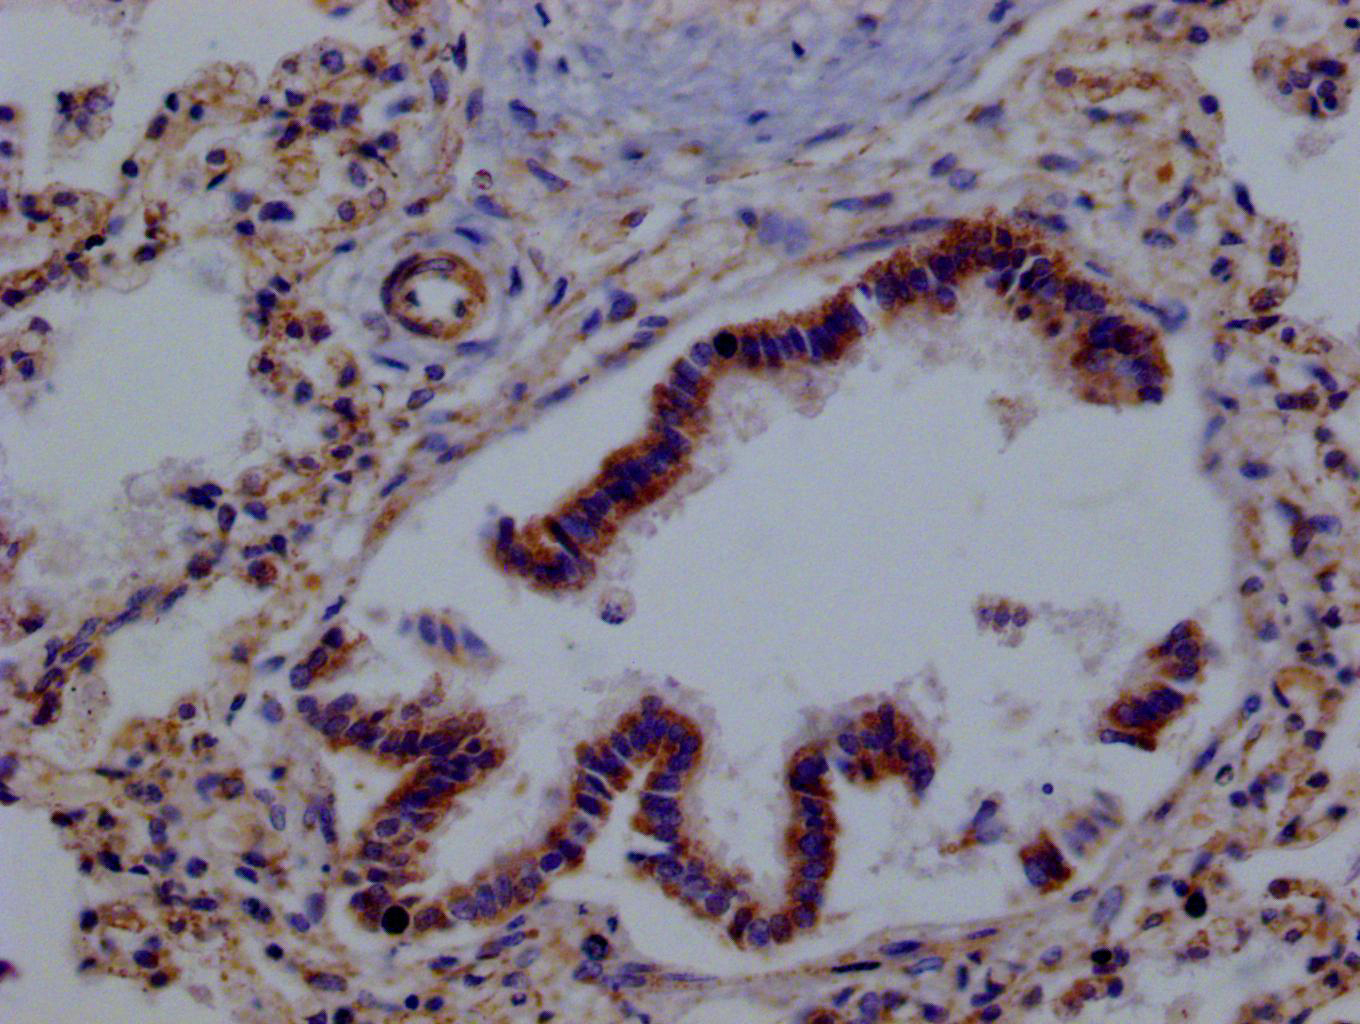

IHC image of CSB-RA437344A0HU diluted at 1:100 and staining in paraffin-embedded human lung tissue performed on a Leica BondTM system. After dewaxing and hydration, antigen retrieval was mediated by high pressure in a citrate buffer (pH 6.0). Section was blocked with 10% normal goat serum 30min at RT. Then primary antibody (1% BSA) was incubated at 4°C overnight. The primary is detected by a Goat anti-rabbit polymer IgG labeled by HRP and visualized using 0.05% DAB.